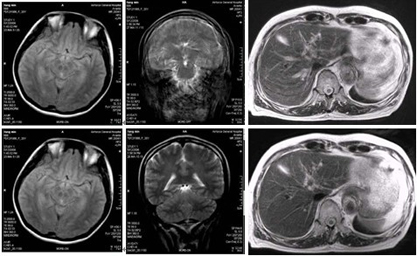

核磁共振仪属大型影像诊断设备,成像技术先进,能够完成许多影像检查设备所不能完成的诊断,具有多方向(横断、冠状、矢状及任意方向切面)和多参成像、高度的软组织分辨能力,无需使用对比剂即可显示血管结构等独特的优点。对神经系统、血管瘤、动脉夹层、血管畸形、胆道以及泌尿系结石、肿瘤、梗阻的诊断具有极大的临床价值,特别是作为颅脑疾病、骨关节病变和软组织病变的首选检查,除此之外,对心脏、大血管等普通低场磁共振机无法诊断的疾病,核磁共振机均能提供清晰、可靠的诊断影像,为临床、教学及科研提供了更多、更新的诊断方法和思路,也为患者提供了便利条件。